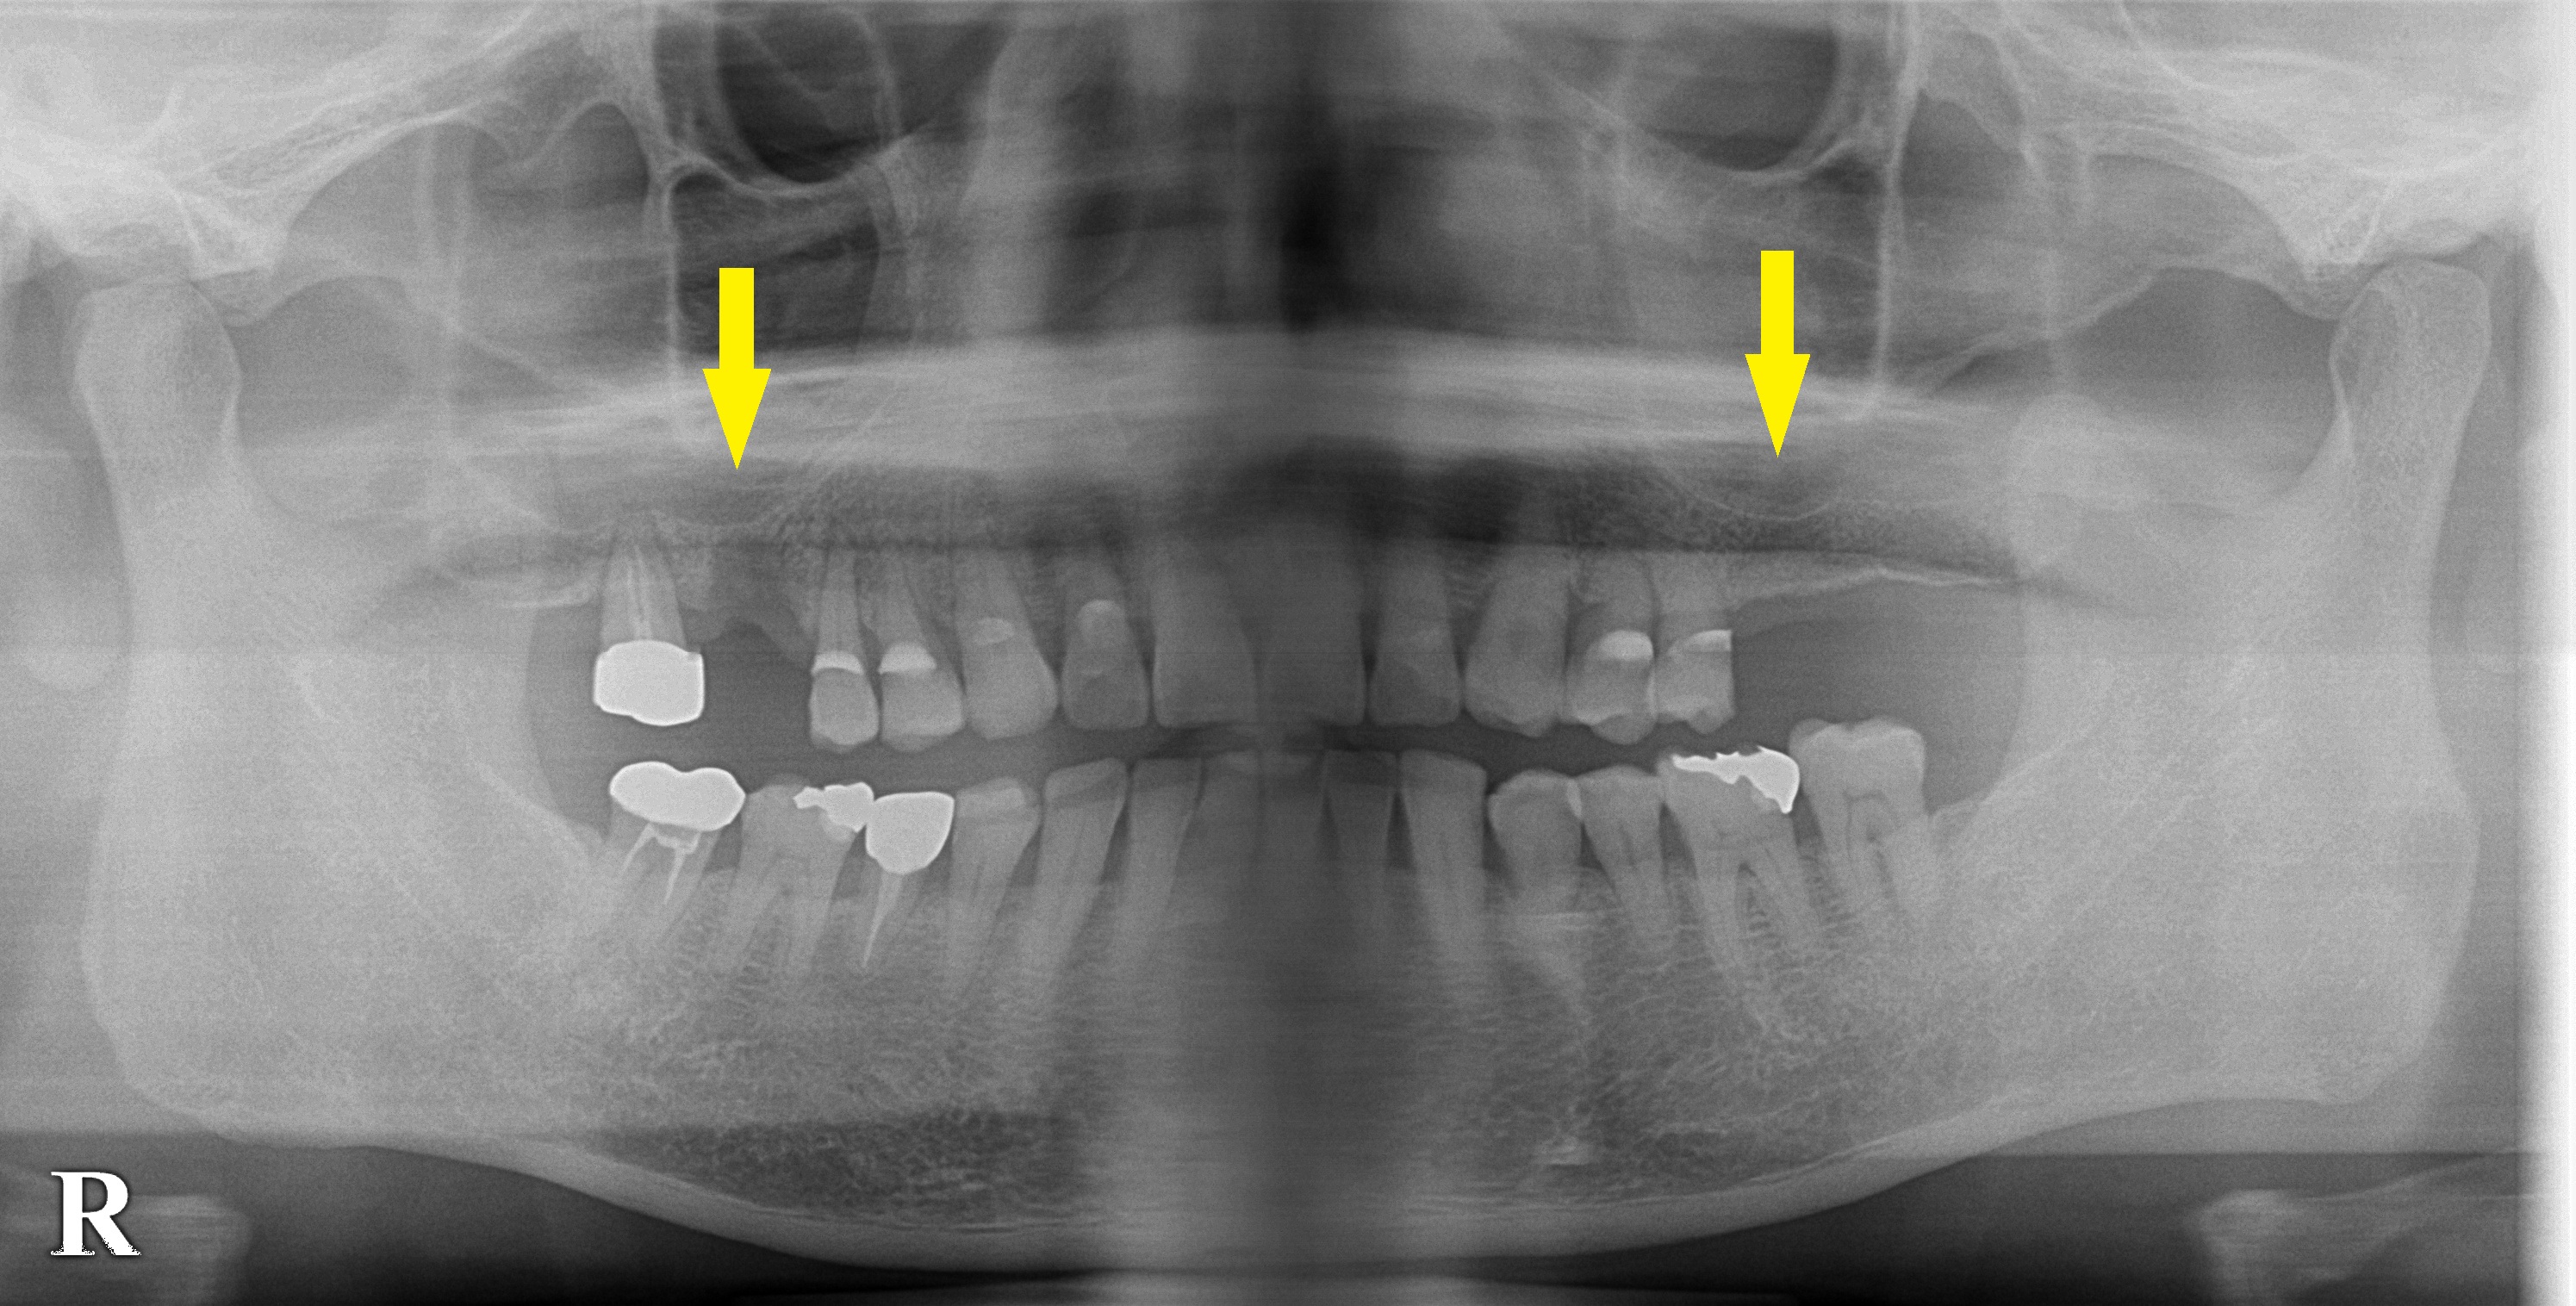

以前より左上顎大臼歯がない状態で過ごされてきたのですが、最近になって右上顎の第一大臼歯が抜け、いよいよ咬みづらくなってきたため、インプラント治療を希望されて、当院に相談に来られました。

右上顎は、抜けたばかりですので、しばらく治癒を待って、インプラント埋入を行なうこととしました。

左上顎は、すぐに手術可能な状態でしたので、本日インプラント埋入術を行いました。

骨が薄かったため、ソケットリフトという骨造成術を合わせて行いました。